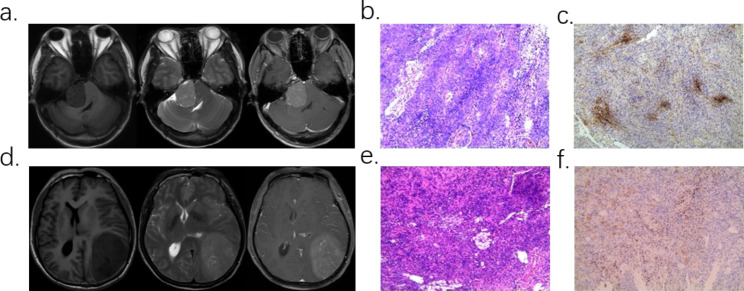

Fig. 1.

Two case examples. a-c. Patient with WHO I meningioma, Ki-67 was 5-10%. a. T1WI, T2WI, T1CE sequence MRI image. b-c. Pathological sections and immunohistochemical staining. d-f. Patient with WHO II meningioma, Ki-67 was 2-3%. d. T1WI, T2WI, T1CE sequence MRI image. e-f. Pathological sections and immunohistochemical staining